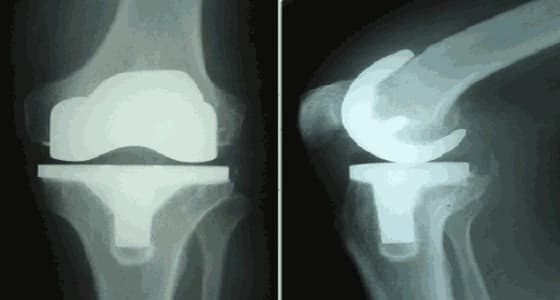

نجح الأطباء في مكة المكرمة ، في إجراء عملية جراحية تضمنت تغيير ركبتي مريض كان يعاني من خشونة وتقوس بدرجة 40 لمدة عامين.

وأكد الدكتور عبدالظاهر الساعاتي الذي أجرى العملية أن الصعوبة كانت تكمن في أنها للركبتين معًا، والمريض كان يعاني من تآكل في عظام الركبتين بسبب الخشونة.

ومن جانبه أكد المريض أنه الآن يمارس حياته بشكل طبيعي بعد إجراء العملية، موجهًا الشكر للأطباء المميزين المؤهلين لإجراء تلك العمليات.